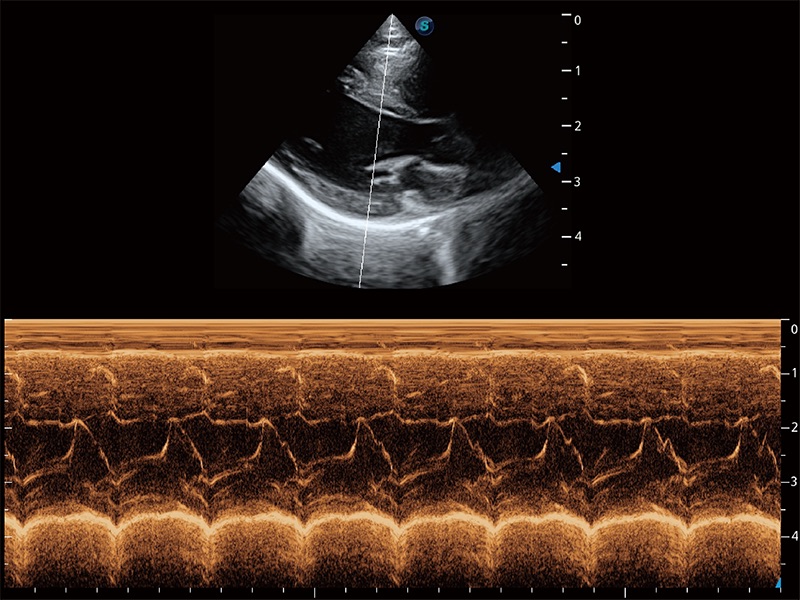

通過360度任意調(diào)節(jié)3條M型取樣線,在同一心動周期上觀察心臟不同位置的運(yùn)動曲線,得到準(zhǔn)確的心功能測量數(shù)據(jù),有效評估心肌運(yùn)動及左心室功能。